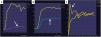

Recordemos que los tumores borderline con características radiológicas específicas y los tumores con grasa con una morfología diferente del quiste dermoide, aunque tengan una captación de contraste con curva de bajo riesgo, se prefiere considerarlos O-RADS RM Score 4 y operarlos en un centro oncológico especializado (fig. 10).

Teratoma inmaduro. En las imágenes observamos una lesión solidoquística con áreas captantes que muestran una curva de riesgo intermedio (C) y zonas hiperintensas en T1 (no imagen) y T2 (A), que se suprimen en la secuencia T1 FS poscontraste (B), compatible con tejido graso. Recordemos que cualquier lesión solida con tejido graso que no tenga las características típicas del nódulo de Rokitansky debe considerarse maligna y operarse en un centro oncológico realizando revisión anatomopatológica peroperatoria para descartar malignidad.